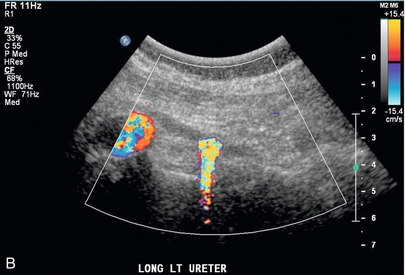

Нефролитиаз

Цветная допплерография должна быть рутинным компонентом ультразвукового исследования почек при подозрении на нефролитиаз. Сама по себе шкала серого имеет низкую чувствительность к небольшим камням в почках. Использование цветного допплера для определения мерцающего артефакта 19 может повысить уверенность в наличии камней в почках, мочеточниках или мочевом пузыре ( рис. 9-7 ). Неровная поверхность камня вызывает доплеровский сдвиг, который проявляется в виде шумного цветового и спектрального сигнала. Это помогает подтвердить, что яркий эхогенный фокус в воротах почки действительно является конкрементом, а не яркой эхогенной жировой тканью ворот почки. Этот метод следует использовать для демонстрации наличия камня, а не для измерения его размера. Это особенно полезное дополнение для оценки дистального камня мочеточника с помощью эндовагинальной техники, когда во время беременности обнаруживается расширенная собирательная система верхней почки ( рис. 9-8 ).